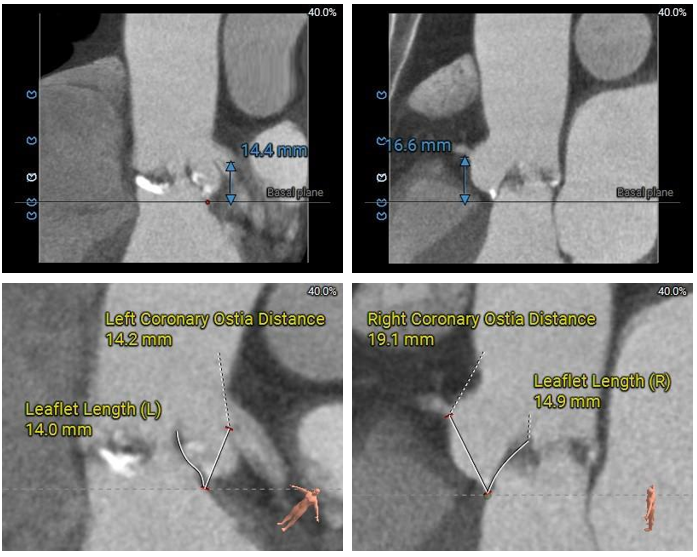

冠脉分析

左冠开口较低,双侧瓣叶冗长,预估双侧冠脉均存在一定遮挡风险。

多平面分析

冠脉开口高度可,未见冗长瓣叶,预估冠脉遮挡风险较低。